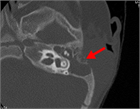

1. 急性中耳炎に罹患する機会が多く、乳様突起が未発達な乳幼児に発症することが多い。

1. 耳後部皮膚の発赤、腫脹、波動、耳介の立ち上り(耳介聳立)が診断のポイントとなる。

1. 重症例では、顔面神経麻痺、頭蓋内合併症などを併発する可能性がある。